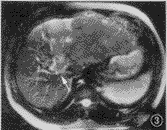

图1~4 男,41岁,肝左叶巨块型肝细胞癌,门静脉瘤栓(箭头)。图1和图2为true-FISP横断及冠状面T2.WI,门静脉呈亮信号,腔内瘤栓清晰显示;图3为TSE T2WI,门静脉瘤栓呈略高信号肿块,显示不及true-FISP;图4为对比增强门静脉MR血管造影,证实门脉瘤栓存在

1.图像质量:图像质量分级评价结果见表1,与TSE序列T2WI相比,true-FISP序列T2.WI可清楚显示肝静脉、门静脉主干及主要分支或属支,血管在此序列上呈高信号,病变对门静脉及肝静脉的侵犯能清晰显示(图1~4)。尽管应用了脂肪抑制,大多数病人的TSE图像仍有由于轻微呼吸运动造成的伪影,而true-FISP图像即使病人不能很好屏气,也没有明显的呼吸运动伪影。靠近肠道(如胆囊窝及其周围)及膈肌面(特别是膈面不平滑的病人)的部分肝脏区域,在true-FISP图像上受气体干扰可出现圆形伪影,酷似肝内病灶或胆囊结石,也可掩盖肝内病灶,TSE图像上不出现类似的伪影。对于脏器的轮廓及肝外结构如胆管、肠管、血管、组织间隙等的显示,true-FISP序列也明显优于TSE序列。

true-FISP选用很短的TR和TE,流动效应几乎可以忽略不计,血液的长T2特点可以得到很好的体现[7,8]。在true-FISP T2.WI中,动脉、静脉都呈现高信号,门静脉系统及肝静脉的解剖结构和病变的侵犯都能清楚地显示,明显优于TSE序列(图1~3),这对于病变范围确定、病变分期分级及制定肝脏肿瘤的治疗方案都有着重要的指导意义,门脉系统的充分显示还有利于门脉高压及其侧支循环的评价,这是目前其他常规MRI序列无可比拟的。